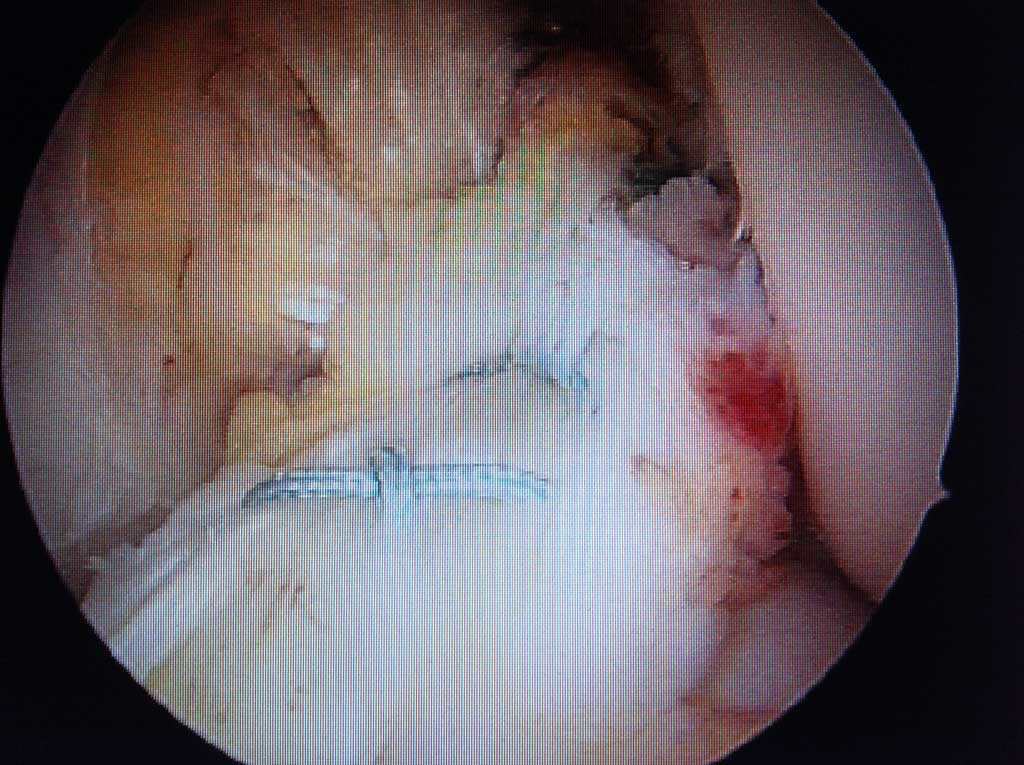

Wichtig ist es dabei, dass durch einen erfahrenen Kniespezialisten beurteilt wird, ob die Beschwerden mit dem Befund bei der klinischen Untersuchung und dem MRT (Kernspintomographie) relevant zusammenpassen. Dann kann nämlich dem Patienten durch eine sehr schonende arthoroskopische Operation gut geholfen werden. Dabei werden entweder bei älterem Meniskusriss die instabilen schmerzauslösenden Anteile entfernt (möglichst wenig und so viel wie notwendig), oder bei frischen Rissbildungen kann Teil oder kompletter Meniskus durch eine Naht erhalten werden. Dies setzt jedoch einen sehr erfahrenen Kniechirurgen auf dem Feld der arthoroskopischen Chirurgie voraus.

Arthroskopische Meniskus - Teilentfernung

Wie läuft die Operation ab ?

Es handelt sich dabei um einen ambulanten Eingriff in unserer OCD Klinik. Die Operation wird in Spinatanästhesie durchgeführt und dauert einige Minuten. Während des Eingriffes kann dem Patienten, auf Wunsch, auch das operative Vorgehen auf grossem LCD Monitor erklärt werden.

Arthroskopische Meniskusnaht

Es ist in unseren Händen ebenfalls ein ambulanter Eingriff in OCD Klinik im Maximilium, welcher je nach Ausdehnung des Risses zwischen 15-30 Minuten in Spinatanästhesie dauert. Der Riss wird in s.g. " all inside " Technik genäht, so dass nicht mehr als 2-3 winzige Stichinzisionen am Knie für den ganzen Eingriff notwendig sind und keine zusätzlichen seitlichen Zugänge angelegt werden müssen. Nicht selten wird auch in der gleichen Sitzung, ebenfalls rein arthoroskopisch das gerissene vordere oder hintere Kreuzband genäht oder mit körpereigener/-n Sehne/-n ersetz.